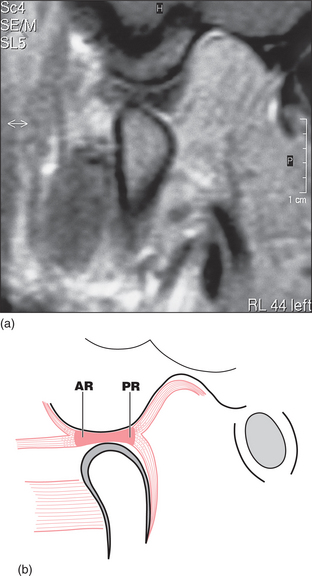

For most people with a clicking TMJ the disc is not in the position described above when the teeth are together. In these people the disc is anteriorly displaced (or anteromedially displaced). This means that the posterior ridge of the disc is actually just in front of the condyle when the teeth are in occlusion (Fig. 16.4). On mouth opening the disc displacement reduces (Fig. 16.5): the disc moves back and the condyle forward relative to each other, in a sudden movement, resulting in the click and a ‘normal’ relationship between the condyle and the disc. This anterior disc displacement with reduction has been demonstrated by cadaveric dissection, arthrography and MRI scanning as the major event associated with clicking of the TMJ. However, it is quite possible for joints without discs (such as finger joints) to click and therefore some clicks of the TMJ are probably due to other joint surface inconsistencies. When the individual with a reducing disc displacement closes their teeth together the disc is again displaced anteriorly.

image

Fig. 16.4 (a) MRI of disc displacement, mouth closed. (b) Diagram of the same.

Fig. 16.5 (a) MRI showing reduction of disc displacement on mouth opening in the patient in Fig. 16.4. (b) Diagram of the same.